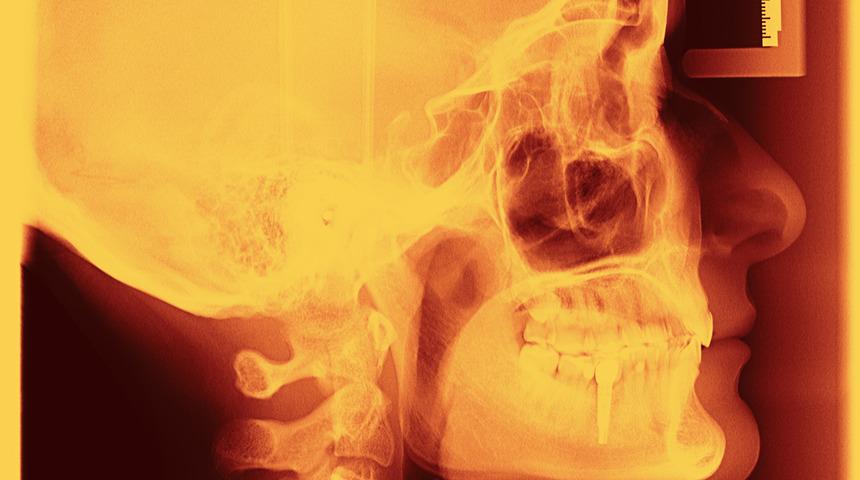

Kameradan aldığı video görüntülerini doğrudan beyne ileten beyin implantı, 6 kör insanın görüşlerini kısmen yeniden kazanmalarını sağladı.

Independent Türkçe'nin haberine göre uzmanlardan oluşan ABD’li ekibin çığır açan çalışmasında beynin görme merkezine (görsel korteks) yerleştirilen elektrotlar görüntüleri gözlüğün üzerinde bulunan video kameradan aldı ve öncesinde hiç görmeyen katılımcıların görmeyi belirli bir seviyede deneyimlemesi sağlandı.

Bu teknoloji her iki göze ve normalde duyu bilgilerini beyne taşıyan optik sinire olan ihtiyacı tamamen ortadan kaldırıyor.